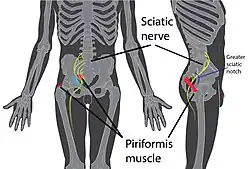

| Location of piriformis syndrome within the body | |

Piriformis syndrome is a condition which is believed to result from nerve compression at the sciatic nerve by the piriformis muscle.[2][5] It is a specific case of deep gluteal syndrome.[6]

The largest and most bulky nerve in the human body is the sciatic nerve. Starting at its origin it is 2 cm wide and 0.5 cm thick. The sciatic nerve forms the roots of L4-S3 segments of the lumbosacral plexus. The nerve will pass inferiorly to the piriformis muscle, in the direction of the lower limb where it divides into common tibial and fibular nerves.[7] Symptoms may include pain and numbness in the buttocks and down the leg.[2][3] Often symptoms are worsened with sitting or running.[3]

Anatomy

The piriformis is a flat, pear-shaped muscle. The thicker side of the piriformis is medial (closer to the center of the body). The function of the piriformis is as an external thigh rotator. When the hip is extended, such as standing, the piriformis rotates the thigh outwards. When the hip is flexed, such as sitting, the piriformis abducts the hip (spreading the legs). The piriformis originates at the anterior surface of the sacrum, passes through the greater sciatic foramen, and inserts at the greater trochanter.[8]

The sciatic nerve is the largest peripheral nerve in the body and innervates significant portions of the skin and muscles of the thigh, leg, and foot. The sciatic nerve originates from spinal nerves L4-S3. It forms in the pelvis from nerves of the sacral plexus, and exits the greater sciatic foramen just underneath the piriformis. A number of anatomic variations exist in the branching pattern of sciatic nerve around the piriformis, such as passing over, through, or under the piriformis, as well as early branching into the tibial nerve and common peroneal nerve before passing the piriformis.[9]